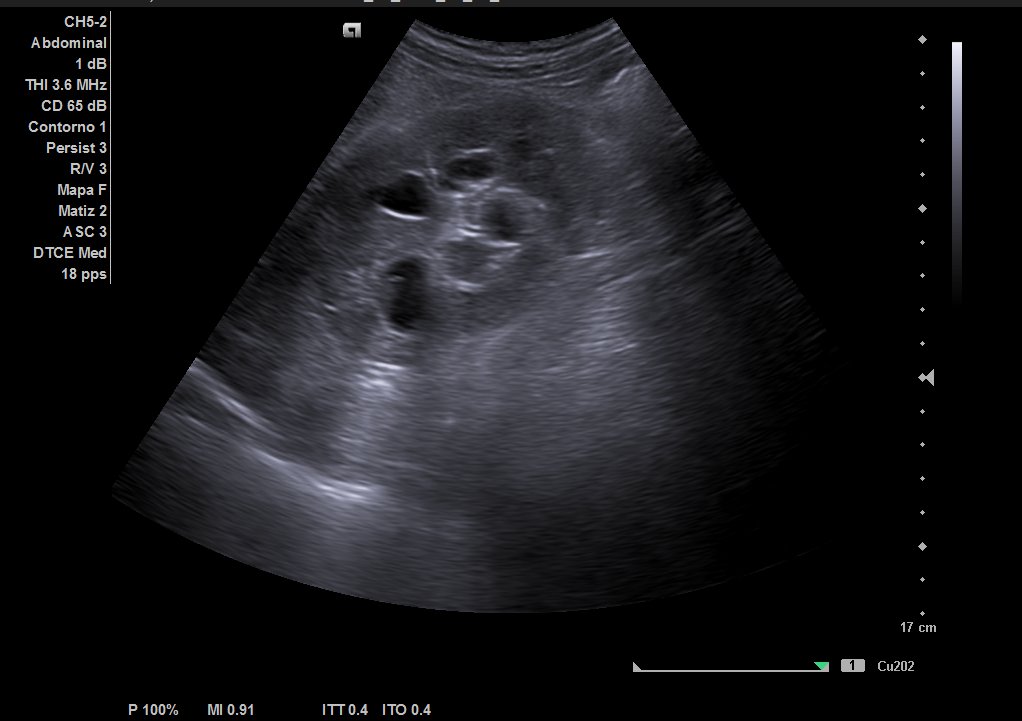

Ecografía reglada: ureterohidronefrosis grado III secundaria a lesión en uréter medio-distal. Vejiga parcialmente replecionada con material ecogénico en suelo vesical con aparente doppler color e interior. Posible coágulo vs lesión subyacente.